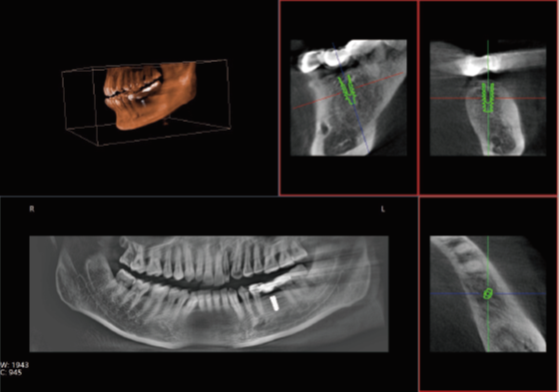

眾所周知,在口腔內種植牙齒是十分精細的手術,沒有先進的可視化影像設備支持的種植牙手術,就猶如盲人摸象,手術效果難以預知。口腔CT影像能測量牙槽骨的高度和寬度,估計種植部位,與下頜阻生磨牙相關的低位下牙槽神經管影響頜骨的疾病的病理學評估。

正常情況下,牙齒的排列不在一個平面上, 且具有一定的生理弧度,普通X線往往使圖像相互重疊,使圖片看不清楚。但是,口腔CT的三維成像對牙體、牙根、牙周膜等微細結構顯示更加清晰。可以幫助醫生了解斷根,牙根內吸收、根管鈣化、牙根結石、牙槽骨退縮等情況,能用于根管治療前尋找根管,術后評估根管充填情況,評估牙周炎程度及預期治療效果等。

正畸治療前的診斷分析是治療成功的重要步驟,口腔CT不僅能提供頭顱側位和曲斷片的信息,還可以評價每個牙齒的排列位置,牙根傾斜度,牙槽骨垂直向、頰舌向的骨量,骨密度等。用于牙列不齊矯正、牙頜面畸形矯正、牙周病輔助正畸。

口腔CT與全身CT相比,具有分辨率高、X射線輻射小、投照時間短、費用低、應用廣泛方便、操作簡單、可以配合第三方軟件獲得更多信息等優點。普愛醫療口腔CT使用脈沖透視采集圖像,在保證成像質量的基礎上,可有效降低患者吸收的輻射劑量。實現數字化三維容積重建,冠狀面、矢狀面、橫斷面的類CT成像效果,重建全景影像,選配牙種植系統,滿足牙周、牙根管、口腔矯形矯正、牙種植等臨床病例提供診斷依據。